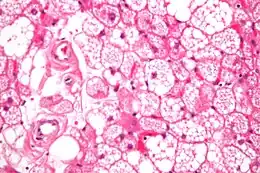

Coupe histologique d'un hibernome en coloration H&E

L'hibernome est une tumeur bénigne développée aux dépens de la graisse brune.

On distingue quatre types histologiques d'hibernome : typique, myxoïde, lipome-like et à cellules fusiformes[1],[2].